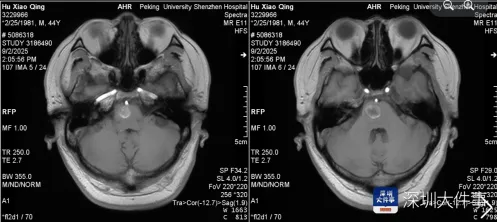

家人紧急将其送往医院,急诊检查结果让所有人揪心——头颅MRI显示,阿伟脑干桥脑右侧存在占位性病变,确诊为海绵状血管瘤并出血。

“脑干是人体的生命中枢,长约8厘米,最宽处仅2厘米,控制着心跳、呼吸、血压等基本生命功能,这个拇指大小的区域密布着关键神经与血管。”

医生介绍,海绵状血管瘤虽名为“瘤”,实则是异常扩张的血管团,约20%发生在脑干,致死和致残率极高,“每一次出血都可能导致灾难性的神经功能损伤,阿伟的肢体无力和言语障碍,说明出血已经影响到重要神经结构。”